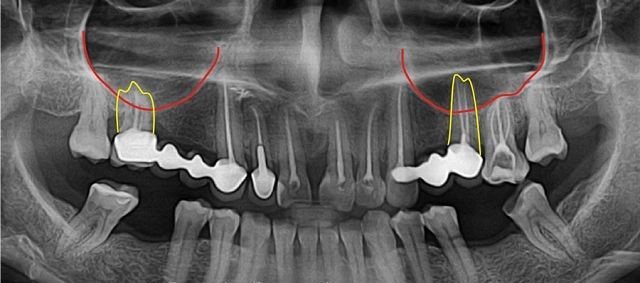

Это осложнение чаще всего возникает при удалении коренных зубов на верхней челюсти корни, которых находятся близко к этой полости.

- Иногда толщина пластинки кости между дном полости корнями зубов не превышает один миллиметр.

- Встречается вариант расположения корня второго и первого моляров, когда они проникают в полость и отграничены от неё только слизистой, которая выстилает пазухи.

- В процессе установки импланта в кость верхней челюсти с последующим протезированием зуба может быть легко повреждена гайморова полость. Это происходит потому, что имплант похож на шуруп и должен быть ввинчен в кость. При дефектах проведения этой манипуляции или анатомо-топографических особенностях у больного может быть повреждена костная пластинка верхней челюсти (неправильно подобран размер импланта, были дефекты подготовки к имплантированию). Врач не учитывает перед постановкой импланта то, что при удалении зуба толщина костной пластинки быстро уменьшается.

Вероятность перфорации пазухи увеличивается при расположении зубного корня в непосредственной близости к ней в момент удаления. Поэтому хирургическое лечение должно проводиться с предельной аккуратностью и последующим рентгенологическими контролем состояния тканей после операции. Также стоматолог контролирует состояние тканей при использовании штифтов для имплантации или при обработке корневых каналов в целях пломбирования, так как велик риск проникновения материала пломбы и обломков корня в гайморову пазуху.